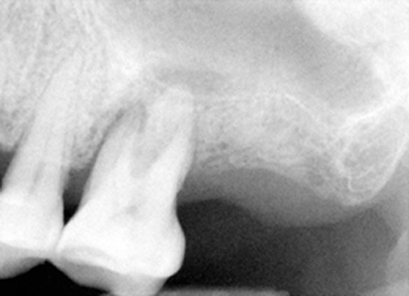

| 图三 术中根尖片插入主牙胶尖 | 图四 术中根尖片牙胶尖側方充填后 |

治疗:局麻,超声洁治4,5,6号牙,橡皮障隔离,开髓,活髓,使用特殊Piezo超声金刚钻头寻找MB2根管口,但是没有找到。使用根尖定位仪,用手用扩大针至15号,然后是用电动扩大针(Dentsply Tulsa Protaper),MB(近中根管),DB (远中根管)扩大到30/.06(锥度)14.5mm, P (鄂侧根管)40/.06 14.5mm,使用大量漂白液(sodium hypochlorite)冲洗和润滑剂,插入相应的主牙胶尖,拍摄根尖片(图三),距离尚可,P 根管最后通到 15mm,用纸尖吸干根管,介入AH Plus paste糊剂,再次插入相应的主牙胶尖,加入附加牙胶尖,侧方挤压充填,再次拍摄根尖片(图四),P根尖可能糊剂超充,去除多余牙胶尖,做轻度垂直挤压充填,使用Cavit暂时封闭根管治疗开口。治疗过程,林太太恶心两次,血压正常,自行好转。